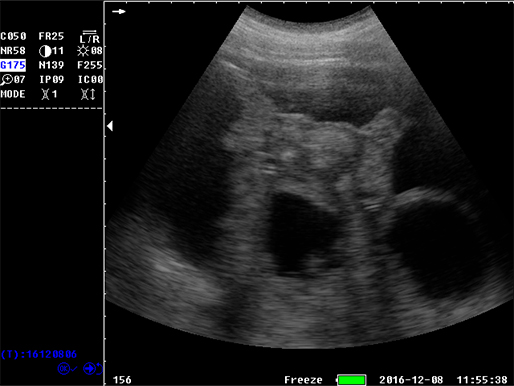

B模式 子宫 牛

B模式 猪孕检

B模式 牛 直肠

牛 直肠

牛未受孕

牛受孕泡

牛受孕35天

猪孕检

猪孕检

猪孕检